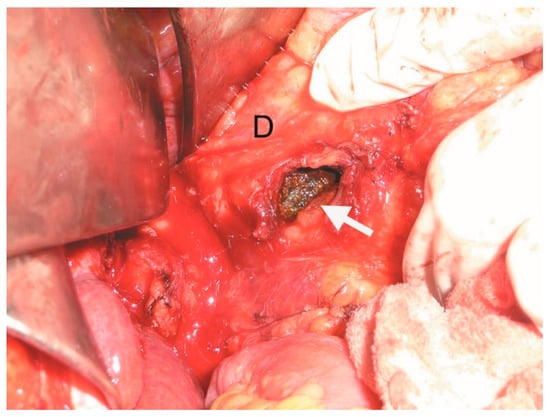

Figure 3.

Intraoperative image showing duodenotomy (white arrow) with the impacted gallstone (D—duodenum).